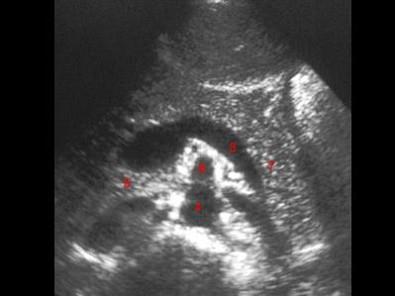

图示7所指部位?(?)A.脾静脉B.胃C.胰尾D.第二肝门E.左肾上腺

问题 图示7所指部位?(?)

选项 A.脾静脉 B.胃 C.胰尾 D.第二肝门 E.左肾上腺

答案 C